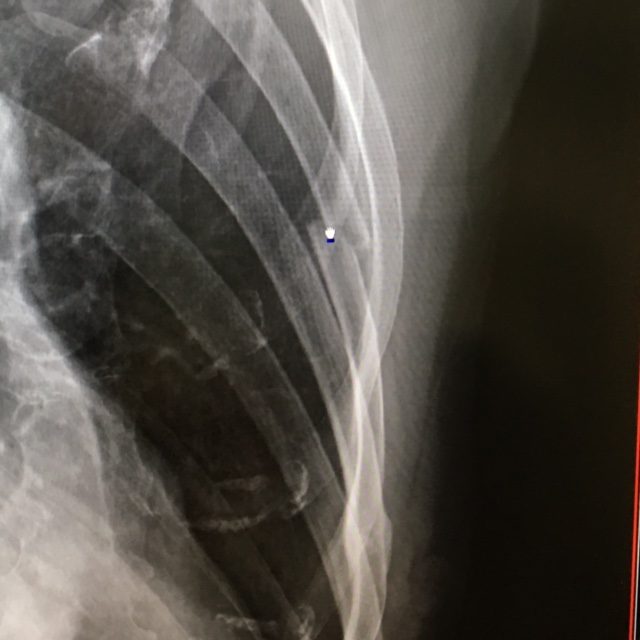

コケた直後からくしゃみや咳をすると痛いし、寝返りも大変だし、今回は原因がはっきりしているから、こりゃひょっとしたら折れているかもと病院に行ったところ・・・、あら折れてるね、と。ヒビが入っているくらいかなと思ったら、ポッキリいってました(涙)。5番目の肋骨らしい。

それにしても、骨折というともっと大げさなイメージでしたが、肋骨を抑えるゴムバンドみたいなのをして、重いものを持たないようにと注意を受け、痛み止めが出て、処置は以上。噂には聞いていましたが、肋骨だからどうしようもないみたい。痛みの出るような動作をせずに過ごし、2週間後にまたレントゲン見せてくださいって。ま、私としても普通に生活できるからいいか。

それと今回レントゲンを撮ってみてわかったのですが、なんと一本下の6番目にも、過去に折れてくっついた形跡が・・・。先生に「前にも骨折してますね」と言われて、「え〜??」みたいな。そういえば、今回ほどではないですが、昨年末に今回と似た症状があり、寝起きが大変だったときがありました。そのときも、もしかして折れているかも?と思ったりもしたのですが、思い当たるはっきりとした原因がなく、2週間ほどで痛みが引いてきたものあって病院に行かないままになったのでした。レントゲンからではいつの骨折跡かまではわからないらしいのですが、そのときかな~?部位もそのへんだったし。

てなわけで、ずいぶん簡単に折れるな〜と情けないような、がっかりしたような気持ちになる一方、自然治癒力ってすごいなと驚いたりもして。しかも、くっつたところはより太くなっていて、頼もしいじゃないの〜と。今回も、おとなしくしてたらそのうちくっつくんでしょうね。